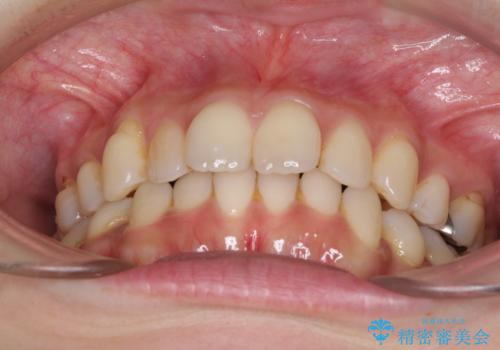

- 上下前歯の叢生を気にして来院された患者様です。

費用を抑え、期間もあまりかけずに治療をしたいとのことで、インビザライン・ライトを用いて矯正治療を行うこととしました。

インビザライン・ライトは、製作できるアライナーの枚数に制限があるため、移動可能な量に限りがあります。

一方で、半年程度で治療を終えることができるため、軽度の歯列不正の患者様には大変お勧めです。